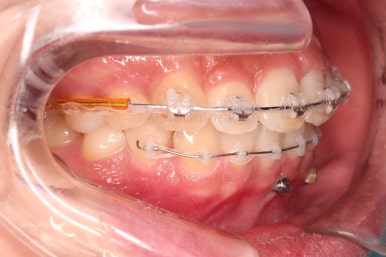

과개교합 개선을 위해서 미니스크류까지 힘을 줘서 아래 앞니를 내려줍니다.

아래 앞니는 브라켓보다는 훨씬 작은 미니튜브 장치를 사용했습니다.

과개교합의 경우 브라켓을 부착하게 되면 씹히게 되어 치료과정이 수월하지 못하기 때문이죠.

중간중간 미니스크류가 빠지든, 위치적으로 좋은 곳을 선택하든 여러 이유로 미니스크류 재식립이 몇 번 있었고요.

부족한 공간은 치간삭제를 통해서 만들어 나갑니다.

디테일을 위해서 윗니는 어금니에도 하나씩 장치를 더 부착했고, 아랫니는 바로 뒷 치아에도 장치를 부착했습니다.

기왕(부분교정임을 감안했을 때) 오래 걸린거 좀 더 완성도를 높이고자 아래 앞니는 설측교정까지 부착했습니다.

역시 미니튜브 장치를 이용했고, 아래 앞니 안쪽에다가 장치를 부착해서 아주 미세한 배열을 맞춰드렸습니다.